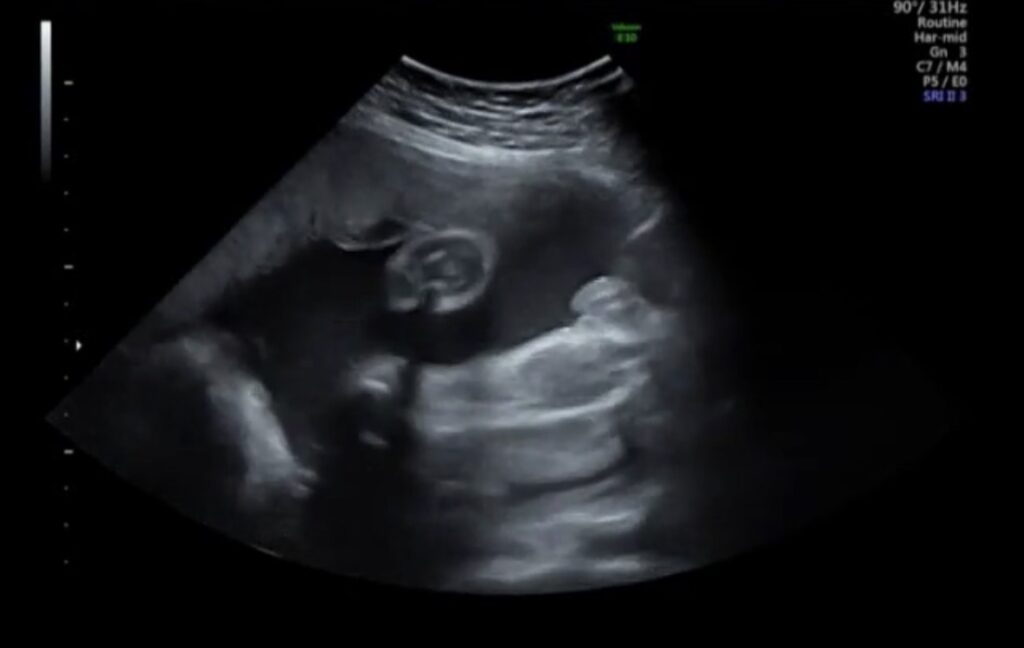

↑この時点のエコーがこちらです。ここで女児判定に変わりました。